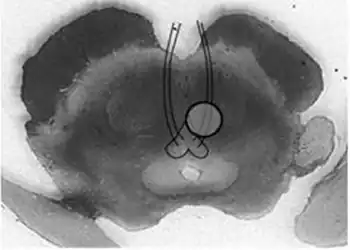

| Benedikt syndrome. Localization of oculomotor fascicle injury and symptoms of Benedkit syndrome. | |

Benedikt syndrome, also called Benedikt's syndrome or paramedian midbrain syndrome, is a rare type of posterior circulation stroke of the brain, with a range of neurological symptoms affecting the midbrain, cerebellum and other related structures.

It is characterized by the presence of an oculomotor nerve (CN III) palsy and cerebellar ataxia including tremor and involuntary choreoathetotic movements. Neuroanatomical structures affected include the oculomotor nucleus, red nucleus, corticospinal tracts and superior cerebellar peduncle decussation. It has a similar cause, morphology, signs and symptoms to Weber's syndrome; the main difference between the two being that Weber's is more associated with hemiplegia (i.e. paralysis), and Benedikt's with hemiataxia (i.e. disturbed coordination of movements). It is also similar to Claude's syndrome, but is distinguishable in that Benedikt's has more predominant tremor and choreoathetotic movements while Claude's is more marked by the ataxia.